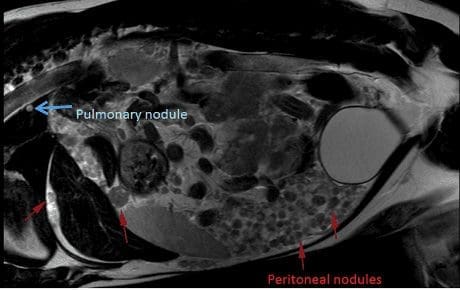

MRI showed widespread peritoneal nodules on a much more dramatic scale than suggested by ultrasound and in addition identified the presence of pulmonary nodules (likely mets) which had not shown up on inflated chest radiographs. The MRI was able to tell us that the mass was most likely originating from the right adrenal gland and was inoperable.